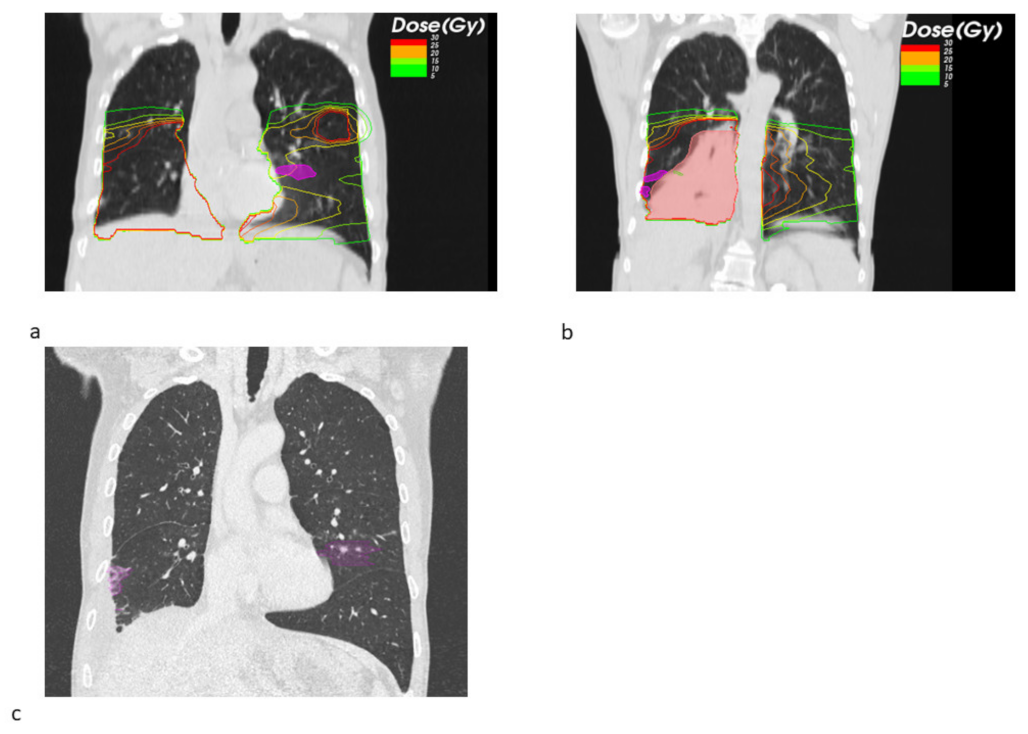

Figure 4. Dose–volume histograms (DVHs) for pneumonitis volume for SBRT + ICB (pink) and SBRT (blue). Doses are indicated in 2 Gy equivalent doses (EQD2). SBRT pneumonitis DVHs are shifted towards higher doses.

Analyzing the DVHs, we noticed a trend towards lower doses for combined SBRT + ICB treatment, as can be seen in Figure 4. This trend was supported by a numerical difference in the area under the curve (AUC), which was smaller for SBRT + ICB compared to SBRT alone (median AUC 1337.37 vs. 5799.10, p = 0.317), even though the data were not significant.